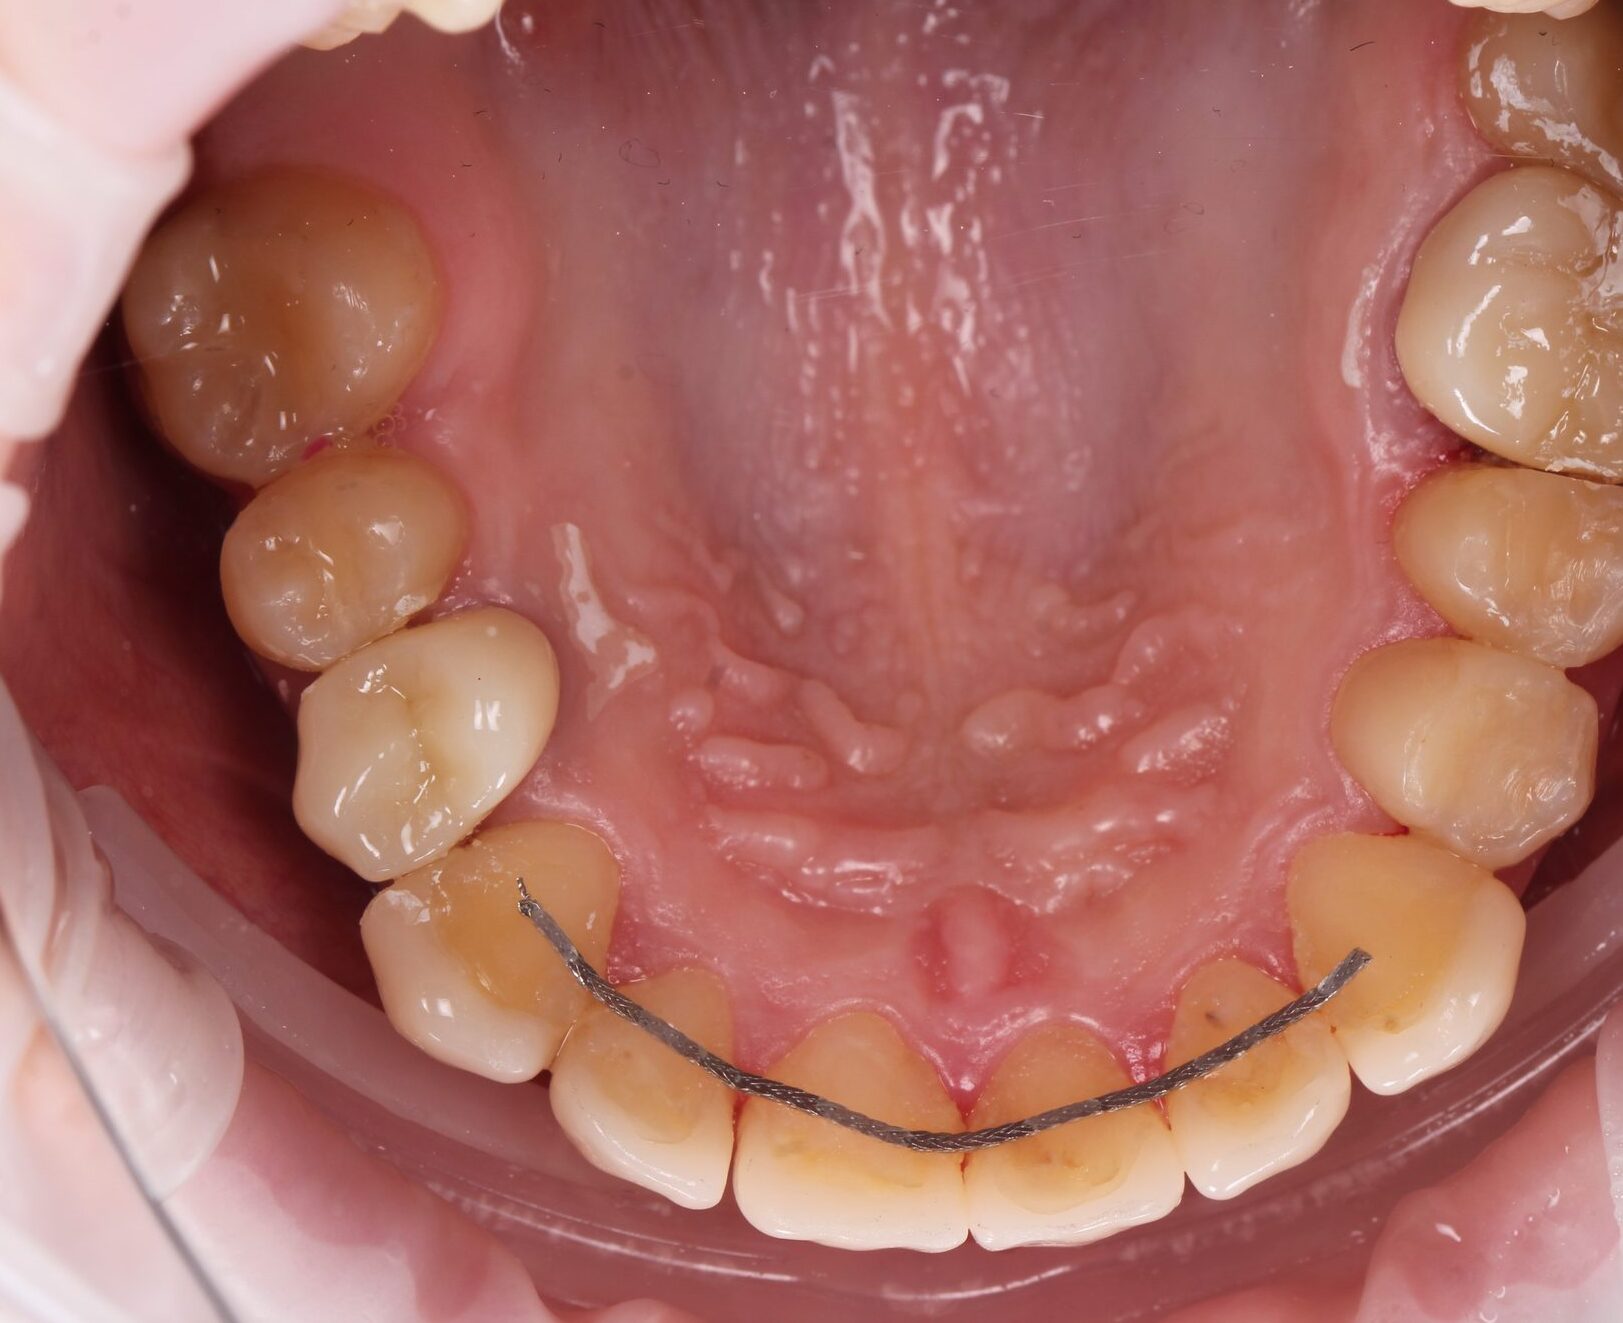

Інна, 24 роки

До

після

Тривалість лікування:

1,5 рік

проведено:

• Професійна Гігієна

• Терапія

• Реставрація

• Лікування кореневих каналів

• Видалення зубів

• Брекет-система

• Імплантація

• Протезування

• Видалення зубів мудрості